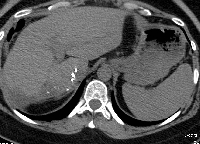

Πρόκειται για γυναίκα ασθενή 47 ετών, η οποία υποβλήθηκε σε κολονοσκόπηση για άτυπα γαστρεντερικά συμπτώματα. Διαπιστώθηκε αδενοκαρκίνωμα σιγμοειδούς με δύο σύγχρονες μεταστατικές εστίες στο δεξιό λοβό του ήπατος (εικόνα 1). Ακολούθησε σιγμοειδεκτομή. Έλαβε 12 κύκλους χημειοθεραπείας με Avastin και FOLFOX. Κατόπιν υποβλήθηκε σε δεξιά ηπατεκτομή (εικόνα 2). Στο παρασκεύασμα φαίνονται οι δύο μεταστατικές εστίες, η μεγαλύτερη εκ των οποίων είναι 4 εκατοστά (εικόνα 3). Ο όγκος του υπολοιπόμενου ήπατος ανήλθε από 39% σε 62%, ένα μήνα μετά την ηπατεκτομή (εικόνα 4). Δεν έλαβε μετεγχειρητική χημειοθεραπεία. Η ασθενής εξακολουθεί να είναι ελεύθερη νόσου.